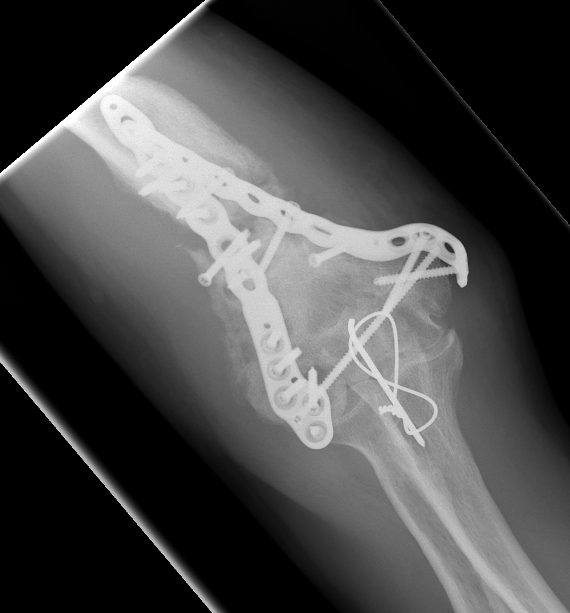

Fixation techniques

Options

Precontoured anatomical plates

Parallel plates v perpendicular plates

Locking v non locking screws

Synthes distal humerus plates surgical technique PDF

Parallel v perpendicular plates

Parallel plates - medial plate on medial column and lateral plate on lateral column

Perpendicular plates - plates at 90 degrees, with lateral plate posterior

- cadaveric model

- biomechanical superiority of parallel plates versus perpendicular plates

- systematic review of 83 studies and 2362 patients

- parallel plating lower incidence of revision for fixation failure (1% v 6%)

- perpendicular plating reduced overall complication (45% v 54%)

- these complications included lower incidence neuropathy, wound dehiscence, and implant prominence